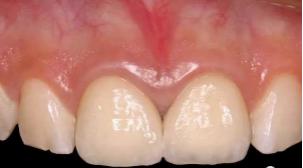

橡皮障下修复治疗中:

修复术后: